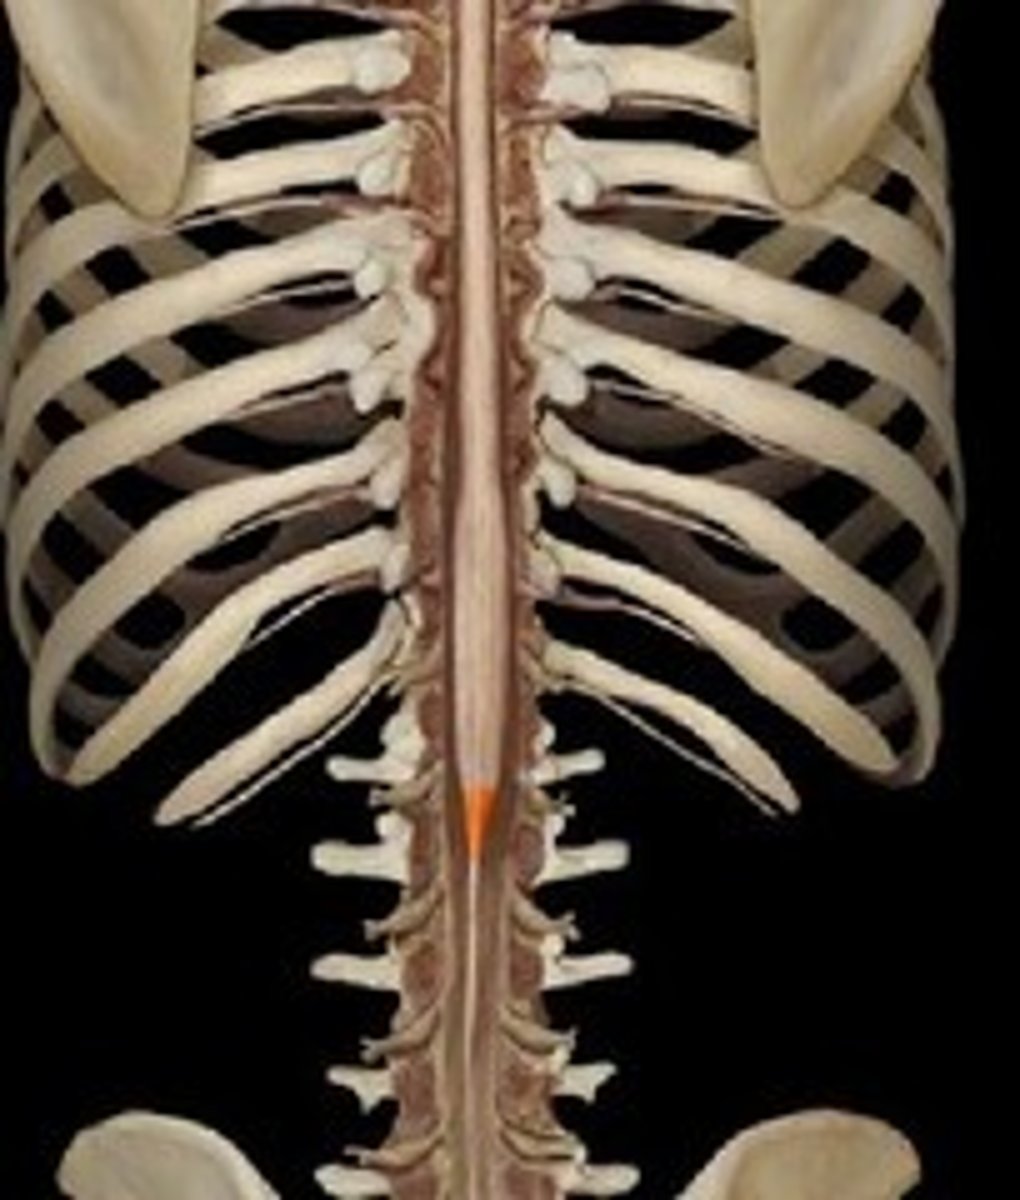

spinal cord

a major part of the central nervous system which conducts sensory and motor nerve impulses to and from the brain; housed within the vertebral canal

cervical region of spinal cord

supplies neck, shoulders, and upper limbs, C1-8

thoracic region of spinal cord

supplies thoracic cage, T1-12

lumbar region of spinal cord

supplies hips & front of lower limbs, L1-5

sacral region of spinal cord

supplies buttock, genitalia, and backs of lower limbs, S1-5

conus medullaris

inferior tapered end of spinal cord

cauda equina

collection of spinal nerves below the end of the spinal cord; below L1 vertebrae

filum terminale

fibrous extension of the pia mater; anchors the spinal cord to the coccyx